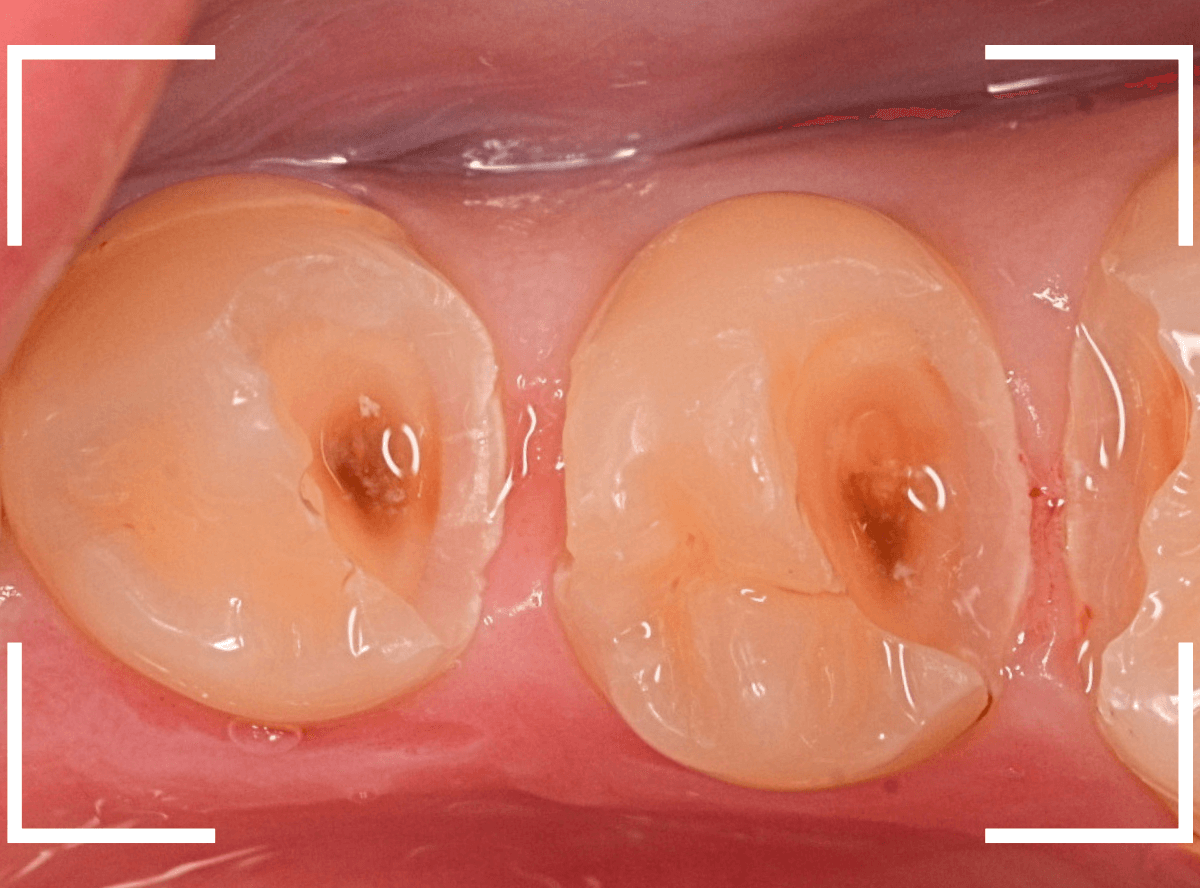

Case.22 痛みはないけど、歯のすきまから大きな虫歯

上の小臼歯の間が虫歯になっていた患者さんです。

症状はありませんし、見た目からも虫歯があるかはわかりませんでした。

レントゲン写真で確認します。

赤い線が虫歯、青い線が歯の神経です。

歯のすきまから両側に虫歯が大きく広がっているのが確認できます。